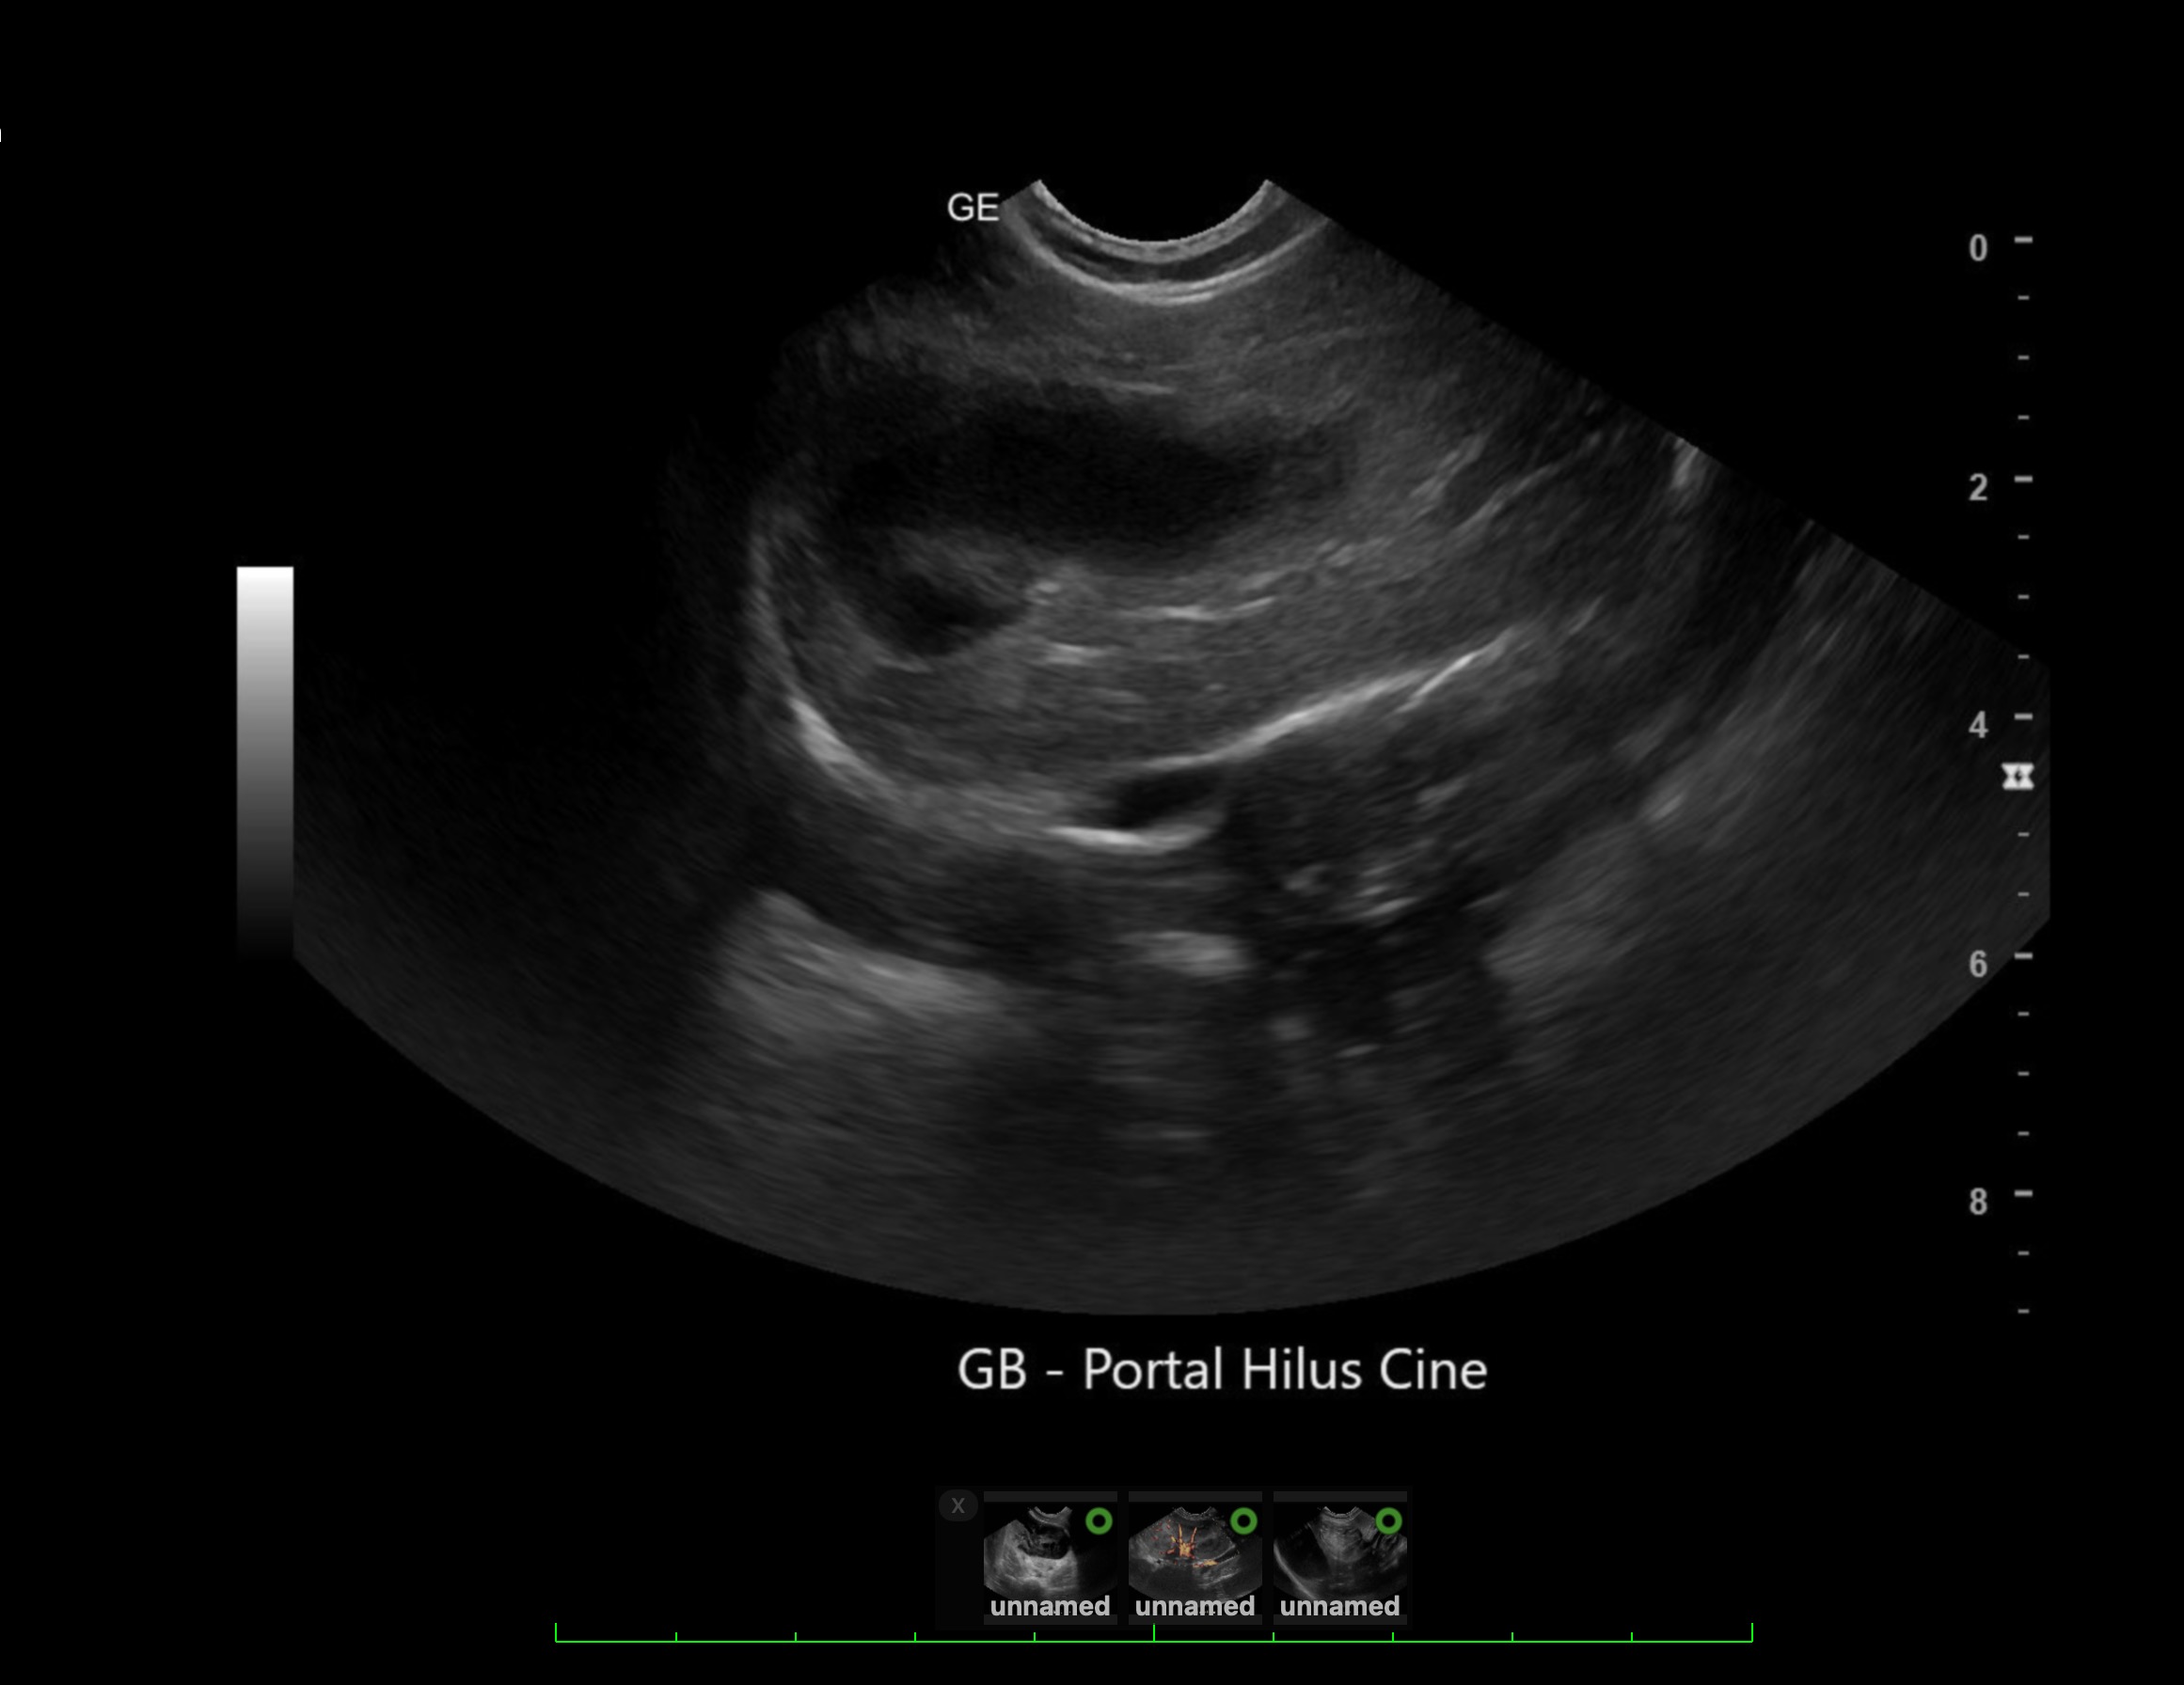

Labwork (fasted): TP 4.5, Alb 2.5, ALP 144, ALT 155, GGT 3, Bili 0.4, Cre 0.3, Cho 51, Amy 266 CBC – HCT 39%, Hgb 12.0 UA – USG 1.030pH 6, 1+ bilirubin, WBC 4-10/hpf, rods 26-50/hpf Negative Accuplex Bile Acids: Pre 299.2, Post-meal – 90.7